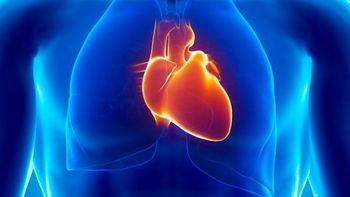

An automated approach can be useful with patients who have indeterminate transthoracic echocardiograms.

More radiologists are providing CT and MRI services, but these studies still fall behind echocardiography and nuclear medicine.